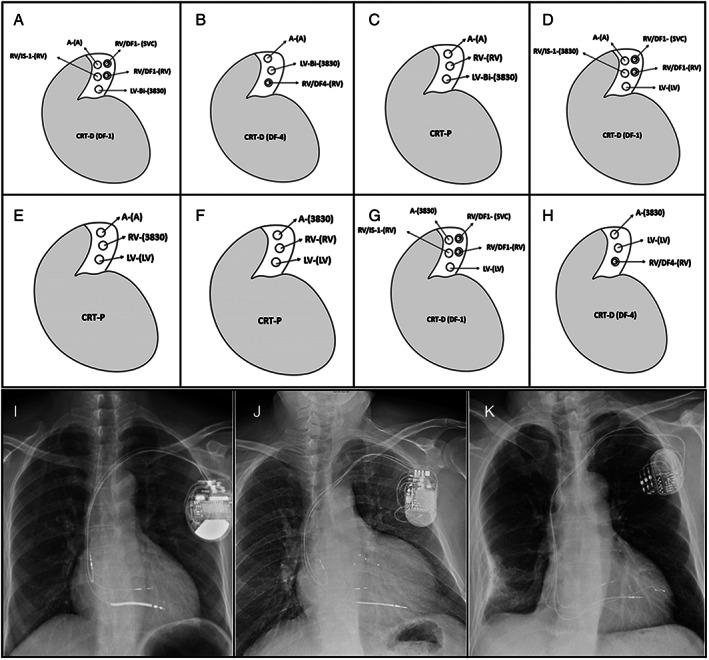

This multicentre observational study aimed to prospectively assess the efficacy of left bundle branch area pacing (LBBAP) in heart failure patients with left bundle branch block (LBBB) and compare the 6-month outcomes between LBBAP and biventricular pacing (BVP).

Consecutive patients with LBBB and left ventricular ejection fraction (LVEF) ≤ 35% were prospectively recruited if they had undergone LBBAP as a primary or rescue strategy from three separate centres from March to December 2018. Patients who received BVP in 2018 were retrospectively selected by using 2 to 1 propensity score matching to minimize bias. Implant characteristics and echocardiographic parameters were assessed during the 6-month follow-up. LBBAP procedure succeeded in 81.1% (30/37) of patients, with selective LBBAP in 10 patients, and 3 of 20 patients combined non-selective LBBAP and LV lead pacing for further QRS narrowing. LBBAP resulted in significant QRS narrowing (from 178.2 ± 18.8 to 121.8 ± 10.8 ms, P < 0.001, paced QRS duration ≤ 130 ms in 27 patients) and improved LVEF (from 28.8 ± 4.5% to 44.3 ± 8.7%, P < 0.001) during the 6-month follow-up. The comparison between 27 patients with LBBAP alone and 54 of 130 matching patients with BVP showed that LBBAP delivered a greater reduction in the QRSd (58.0 vs. 12.5 ms, P < 0.001), a greater increase in LVEF (15.6% vs. 7.0%, P < 0.001), and greater echocardiographic (88.9% vs. 66.7%, P = 0.035) and super response (44.4% vs. 16.7%, P = 0.007) to cardiac resynchronization therapy.

LBBAP could deliver cardiac resynchronization therapy in most patients with heart failure and LBBB, and might be a promising alternative resynchronization approach to BVP.